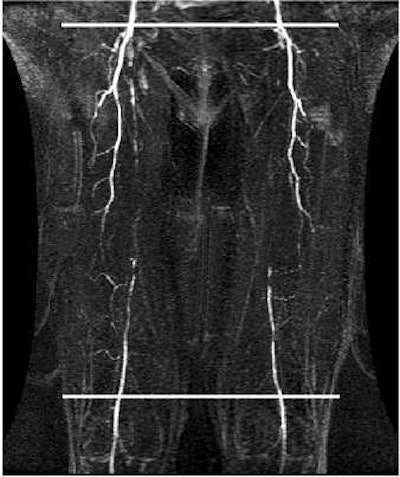

![]() |

| Flow volume curves demonstrate a moderate web-like right SFA stenosis and multiple severe left SFA stenoses. For moderate web-like stenosis, the peak ratio is 1.85, but there is no peak delay and triphasic flow is preserved below the lesion. But for more severe SFA lesions on the left thigh (below), there is an even higher peak ratio, 2.73 and peak delay of about 34 ms. In addition with severe stenoses there is loss of triphasic flow distal to the stenoses. |

The mean peak flow velocity above/below lesion was significantly higher in the segments with severe disease (1.9) or occlusion (1.4) versus normal segments (1.4). In addition, a delay in peak velocity below lesions showed significant positive correlation with lesion severity, the authors stated in their abstract.

The mean flow volume above/below lesions was 3.9 in occluded vessels and 2.3 in normal volunteers. The group found that flow curves tended to change from triphasic to biphasic or monophasic below moderate to severe stenoses (21 of 35) and occlusions (33 of 35).